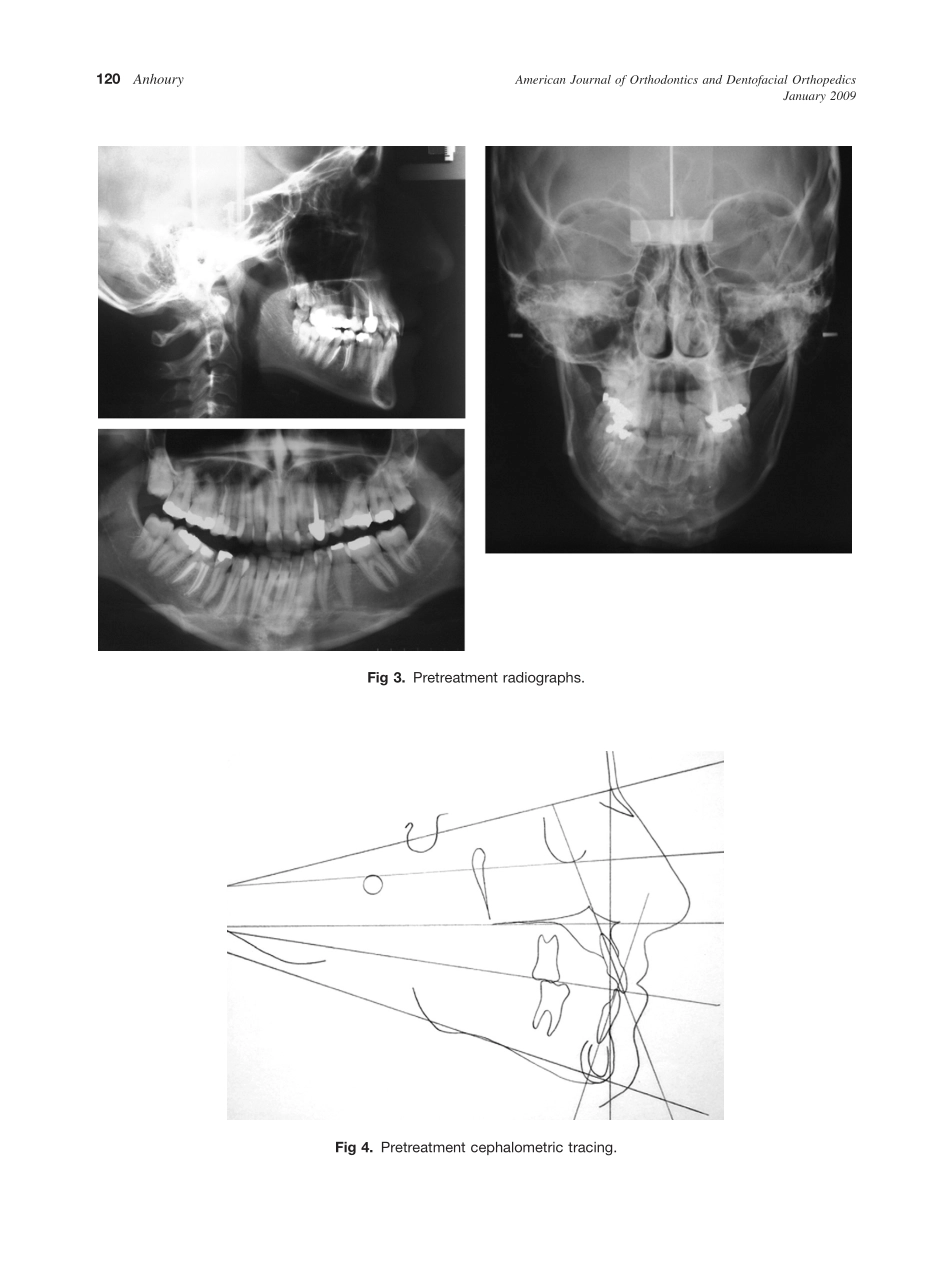

CASEREPORTNonsurgicaltreatmentofanadultwithmandibularasymmetryandunilateralposteriorcrossbitePatrickS.AnhouryBeirut,LebanonThepatientwasawoman,24years8monthsold,withmandibularasymmetryresultinginau...